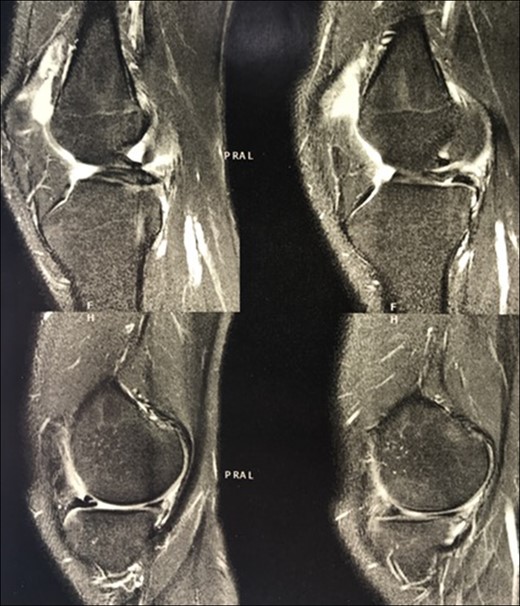

Radiographic images of the knees in AP (anteroposterior) and Lateral views and the panoramic of lower limbs (Fig. 1) were taken and confirmed a case of type 1 A fibular hemimelia on the affected side.

AP radiographic view of the knees (A) and lateral view of left knee—affected (B). AP (C) and lateral view (D and E) of the ankles. Note in (A) tibial spines hypoplasia of left knee, and in (C) left tibiotarsic joint dysplasia with fibular shortening, also noted in (D).